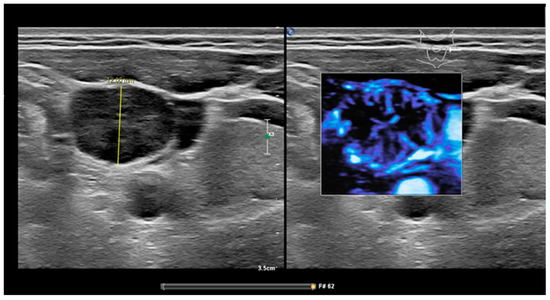

Figure 3.

Ultrasound features of a benign node. (a) Hilum sign in a benign node, no peripheral vascularity. (b) Measurement RI 0.67.